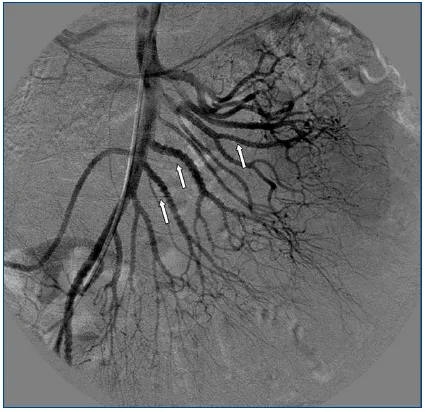

- Presents with fever, myalgia, abdominal pain; "rosary sign" on angiography (aneurysms).

- Angiography reveals multiple aneurysms and stenoses.

⭐ High-Yield: PAN characteristically spares the pulmonary arteries. The "beads on a string" appearance on renal or mesenteric angiography is a classic finding.

- PAN: Angiography reveals microaneurysms and stenoses in renal, mesenteric, or hepatic arteries ("rosary sign" or "beads-on-a-string"). A key alternative when biopsy is inaccessible.